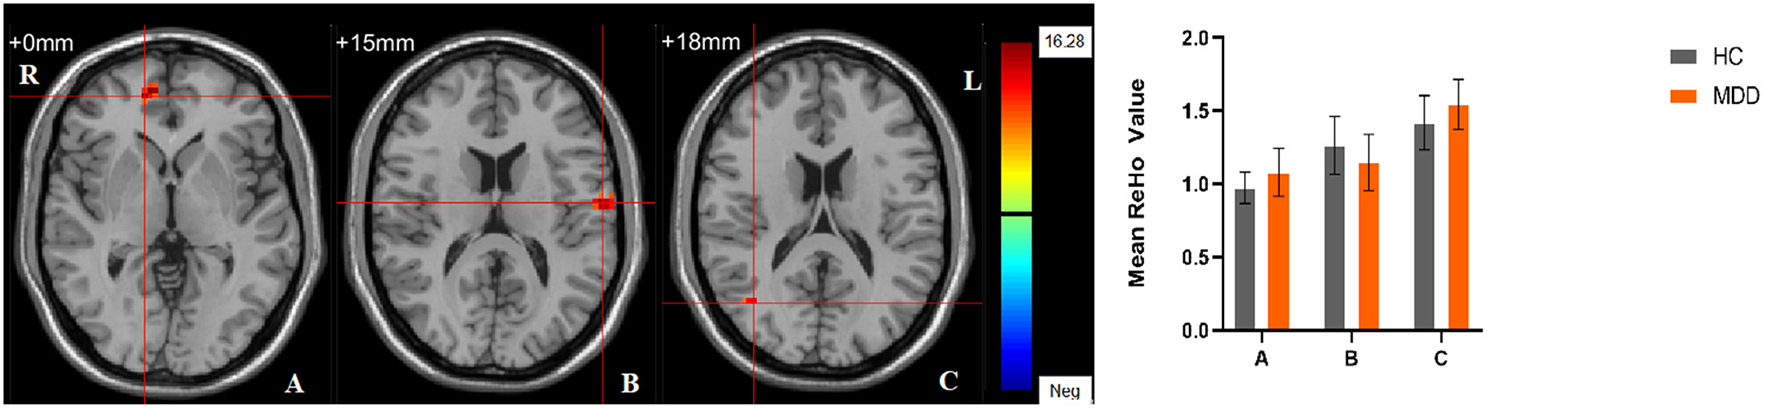

Significant different ReHo values in the main effect of diagnosis were observed in the right superior medial frontal gyrus, left postcentral gyrus, right middle temporal gyrus. The ReHo values in patients with MDD was significantly increased in the right superior medial frontal gyrus, right middle temporal gyrus, and significantly decreased in the left postcentral gyrus, compared with HCs (Table 4, Figure 4). In main effect of sex, significant different ReHo value were observed in the bilateral superior temporal gyrus, bilateral lingual gyrus, bilateral calcarine, right orbital inferior frontal gyrus, right orbital middle frontal gyrus, right postcentral gyrus, left middle occipital gyrus, left dorsolateral superior frontal gyrus, left middle temporal gyrus. The female participants exhibited significantly increased ReHo in the left dorsolateral superior frontal gyrus, left middle temporal gyrus, and significantly decreased ReHo in the bilateral superior temporal gyrus, bilateral lingual gyrus, bilateral calcarine, right orbital inferior frontal gyrus, right orbital middle frontal gyrus, right postcentral gyrus, left middle occipital gyrus compared to male participants (Table 4, Figure 5). The left Calcarine, right median cingulate gyrus, left dorsolateral superior frontal gyrus were significantly observed in diagnosis sex interaction. A post hoc test indicated that women with MDD had significantly decreased ReHo value in the left Calcarine compared with HC females (P < 0.005, Bonferroni correction) and men with MDD (P < 0.005, Bonferroni correction). In the left dorsolateral superior frontal gyrus, women with MDD had significantly decreased ReHo value compared with HC females (P < 0.01, Bonferroni correction), while men with MDD had significantly increased ReHo compared with HC males (P < 0.01, Bonferroni correction) and women with MDD (P < 0.001, Bonferroni correction). Furthermore, the ReHo in the right median cingulate gyrus of HC males was higher than that in HC females (P < 0.005, Bonferroni correction), and men with MDD (P < 0.001, Bonferroni correction) (Table 4, Figure 6).

FIGURE 6

www.frontiersin.org

Figure 6. The diagnosis group × gender group interaction. Regions with diagnosis group × sex group interactions include (A) The left Calcarine; (B) The right median cingulate gyrus; (C) The left dorsolateral superior frontal gyrus (cluster-level threshold of p < 0.05 after GRF correction). The color bar represents the range of F values. R = right, L = left. The graph shows the ReHo values (mean ± standard deviation) extracted from regions with the diagnosis groups × sex group interaction. The Y-axis represents ReHo values. The X-axis represents regions with the diagnosis groups × gender group interaction. ****p < 0.001; ***p < 0.005; **p < 0.01.